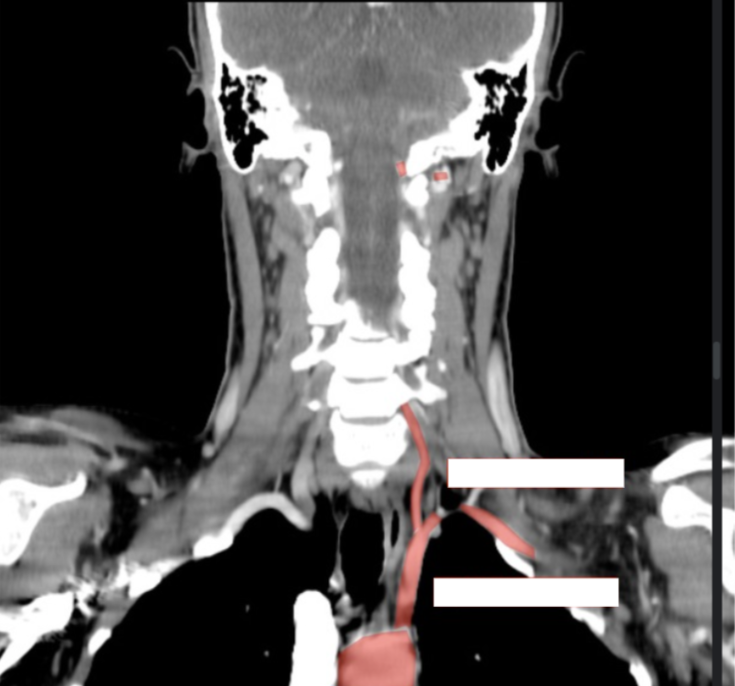

What arteries are these?

Please label the following arteries